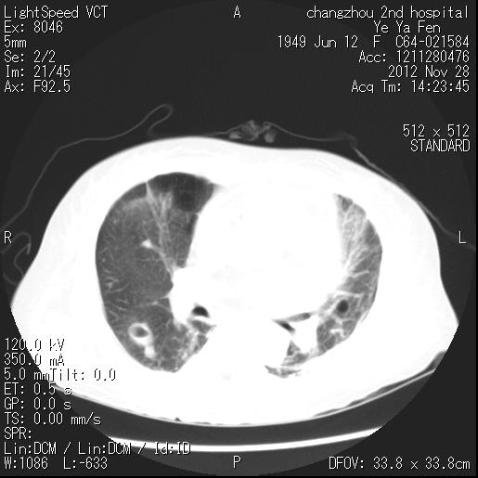

肺部CT检查